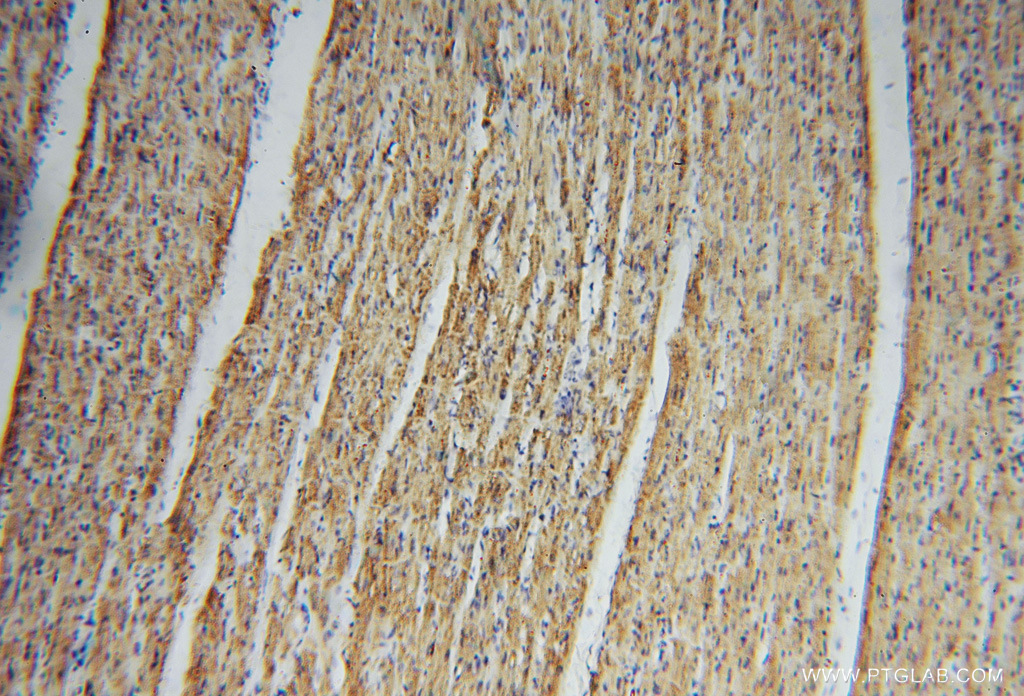

Supportive validation

- Submitted by

- Proteintech Group (provider)

- Main image

- Experimental details

- Immunohistochemical of paraffin-embedded human heart using 16131-1-AP(CS antibody) at dilution of 1:100 (under 10x lens)

- Sample type

- tissue